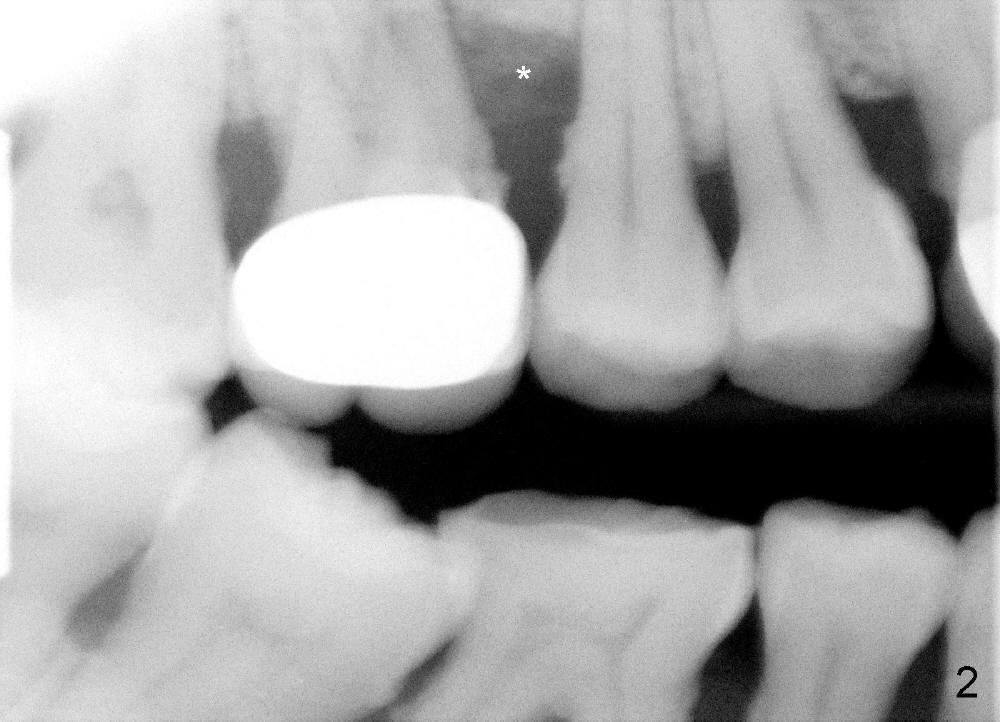

The tooth #3 of a 41-year-old lady is peirodontally compromised (Fig.1 (trimmed panoramus), 2 (PA)) with a large bony defect with the neighboring tooth (Fig.2 *). A large immediate implant is planned to be placed in the basal bone (7 or 8x17 mm, green box) to increase primary stability and reduce the amount of the bone graft to be used (Fig.3 (CT sagittal section),4 (coronal)). If the immediate implant is placed first, there is a limited space (Fig.3 arrows) to place bone graft (red circles) in the hidden areas. Therefore, it would be much easier to bone graft (mixture of autogenous bone, allograft and synthetic bone) first, packed tightly against the mesial, distal, buccal and lingual walls without blocking the entrance to the osteotomy just formed. In spite of the fact that the patient has severe periodontal disease, the bone density of the basal bone is high (Type I/III, Hounsfield units (500-1500)). Reamers will be used to create osteotomy and the autogenous bone will be saved and reused later on.